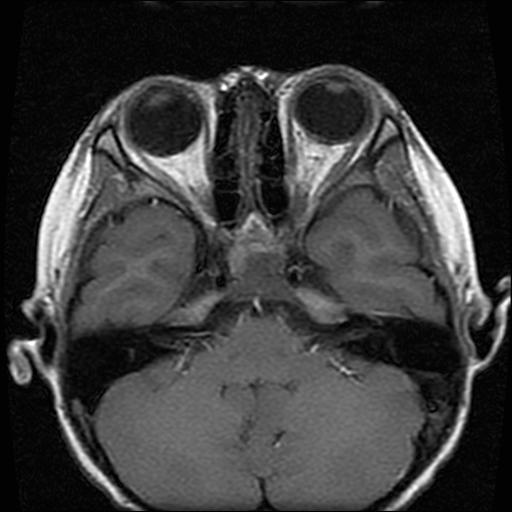

标题: PED0377: 6岁小儿,左侧视神经瘤术后

6岁小儿,左侧视神经瘤术后。现左侧视力减退。